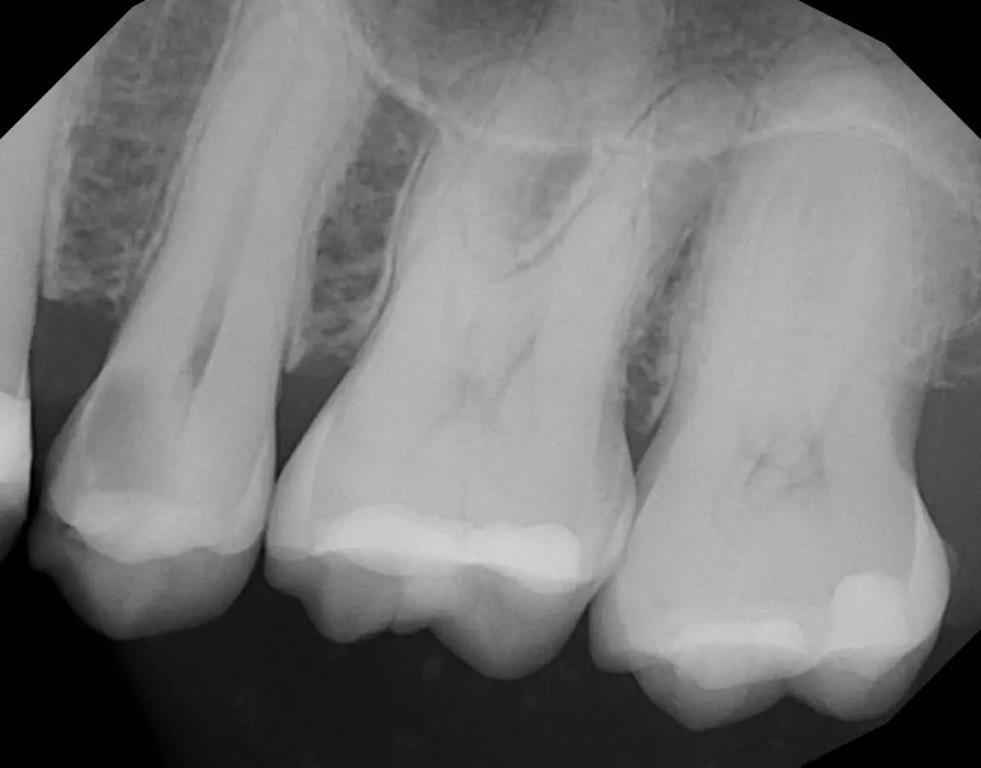

34-летняя пациентка обратилась с жалобами на болевую и температурную чувствительность в задней правой части верхней челюсти. При клиническом обследовании был выявлен кариес на дистальной стороне второго моляра, и была сделана периапикальная рентгенограмма (фото 10). Рентгенологически был подтвержден глубокий кариес на дистоокклюзионном участке зуба №17, который находился очень близко к пульпе. Периапикальной патологии не наблюдалось. Чтобы убедиться в жизнеспособности пульпы зуб подвергли испытанию холодом (фриз-тест). При проведении фриз-теста была отмечена слабая реакция, которая немедленно прошла, когда холод был удален с зуба, что указывало на то, что зуб был жизненно важным. Пациентке сообщили, что в результате удаления кариеса скорее всего, произойдет обнажение пульпы, и поэтому может потребоваться эндодонтическое лечение. Либо же оно будет необходимо позже после лечения пульпы. Лечение будет состоять из лазерной обработки пульпы, если не возникнет большого воздействия, с последующим восстановлением культи зуба и реставрацией полной коронкой. Пациентка согласилась на рекомендованное лечение.

Фото 10: Периапикальная рентгенограмма, сделанная до операции, демонстрирует глубокий кариес с дистально-окклюзионной стороны и минимальное количество зубной субстанции над пульпой.

В буккальном преддверии ввели местный анестетик. Кариес и пораженная структура зуба были удалены с помощью твердосплавных и алмазных боров. Обнажения пульпы не наблюдалось, но была отмечена тонкая структура зуба, покрывающая пульпу (фото 11). Nd:YAG-лазер был настроен на абляцию и воздействовал на область над тонким слоем дентина, покрывающим пульпу, при 50-75 Дж. Затем лазер использовался на той же мощности до 162 Дж для стерилизации окружающих структур зуба и для биостимуляции, как описано в предыдущем случае. Для покрытия нижележащей пульпы было нанесено небольшое количество стеклоиономерного цемента GC FujiCEM. Затем на окружающую здоровую структуру зуба было нанесено покрытие из смолы RelyX Unicem, чтобы обеспечить хорошее сцепление материала культи с дентином. Подготовка коронки на зуб была завершена. Был сделан слепок, изготовлена временная коронка и зацементирована с помощью цинкоксидэвгенольного цемента IRM (Dentsply Sirona). Пациентка вернулась для завершения установки коронки через две недели и сообщила в период, прошедший с момента ее предыдущего обращения чувствительности, не наблюдала. Временная коронка была снята, на окончательная коронка была установлена с помощью самоадгезивного композитного цемента RelyX Unicem, проверена и скорректирована окклюзия.

Фото 11: Пульпарная ткань видна под тонким слоем дентина после удаления кариеса.

На повторном плановом профилактическом приеме через пять лет была сделана периапикальная рентгенограмма (фото 12). Как было отмечено на предыдущих контрольных рентгенограммах, периапикальная рентгенопрозрачность отсутствовала, что свидетельствует об успешном лазерном лечении в предотвращении периапикальной патологии и инфекции пульпы.

Фото 12: Периапикальная рентгенограмма, сделанная через пять лет после лазерного удаления пульпы и реставрации зуба, не выявила периапикальной патологии.